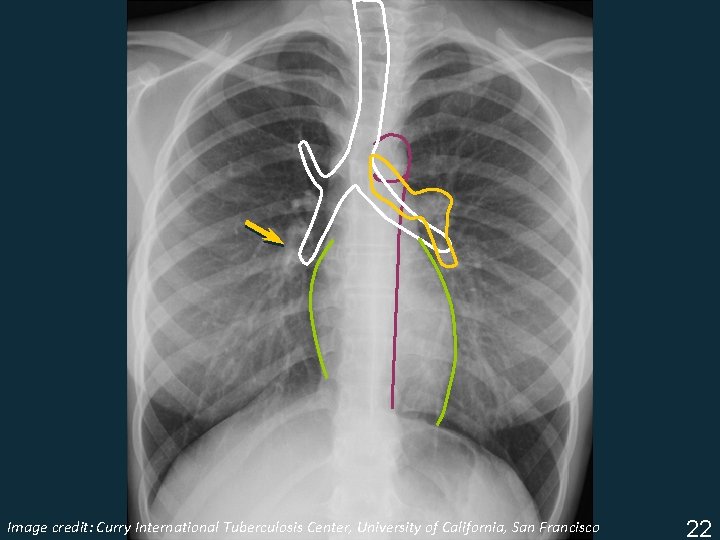

Image Tuberculosis Center, University of California, San Francisco ISTC TBcredit: Training Curry Modules. International 2009 22

§ Aortic arch § Right pulmonary artery § Left pulmonary artery § Trachea & bronchi Image Tuberculosis Center, University of California, San Francisco ISTC TBcredit: Training Curry Modules. International 2009 23

§ Aortic arch Image Tuberculosis Center, University of California, San Francisco ISTC TBcredit: Training Curry Modules. International 2009 23

§ Aortic arch § Right pulmonary artery Image Tuberculosis Center, University of California, San Francisco ISTC TBcredit: Training Curry Modules. International 2009 23

§ Aortic arch § Right pulmonary artery § Left pulmonary artery Image Tuberculosis Center, University of California, San Francisco ISTC TBcredit: Training Curry Modules. International 2009 23